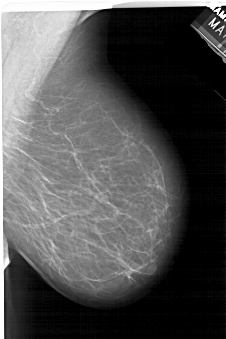

A_1464_1.RIGHT_MLO

RIGHT_MLO LINES 5761 PIXELS_PER_LINE 3826 BITS_PER_PIXEL 12 RESOLUTION 43.5 NON_OVERLAY